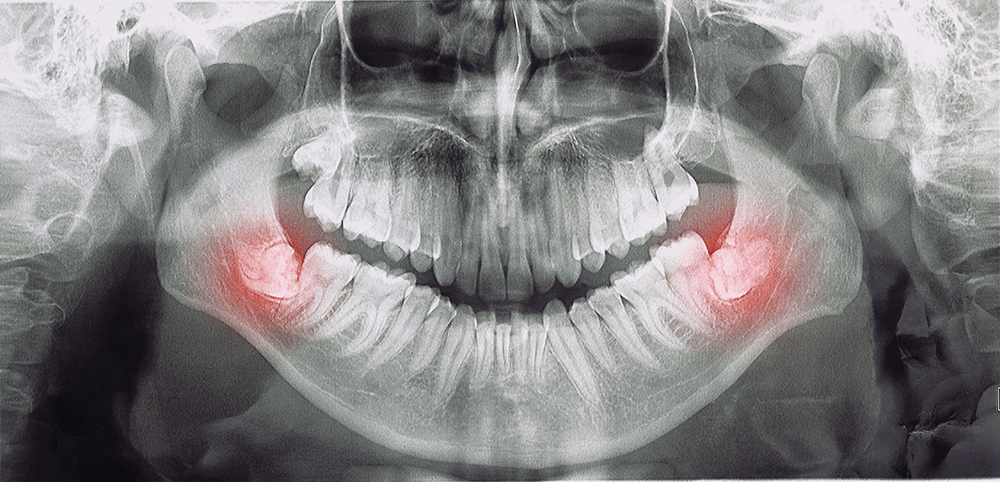

Περιοδοντολογία είναι ο τομέας της οδοντιατρικής που ασχολείται με την θεραπεία και αποκατάσταση του περιοδοντίου. Το περιοδόντιο όπως μας λέει και ο όρος «περί των οδόντων» αποτελείται από τους ιστούς που περιβάλουν τα δόντια, δηλαδή το οστό και τα ούλα.

Βασική νόσος του περιοδοντίου είναι η περιοδοντίτιδα (δηλαδή η φλεγμονή ούλων – οστού) και η αιτία απώλειας των δοντιών των ενηλίκων καθώς στην

Η επινόηση και ανάπτυξη των διεργασιών μεταμόσχευσης οστού έχει οδηγήσει σε διάφορες εφαρμογές όσο αναφορά τη χειρουργική του στόματος, την τοποθέτηση οδοντικών εμφυτευμάτων και την Περιοδοντολογία.

Τα οστικά μοσχεύματα της άνω και κάτω γνάθου μπορούν να εφαρμοστούν για οστική ανάπλαση σε περιοχές, για να καλυφθούν κενά που έχουν δημιουργηθεί λόγω βλάβης ή απώλειας οστού καθώς και για αύξηση του ύψους του οστού κατά